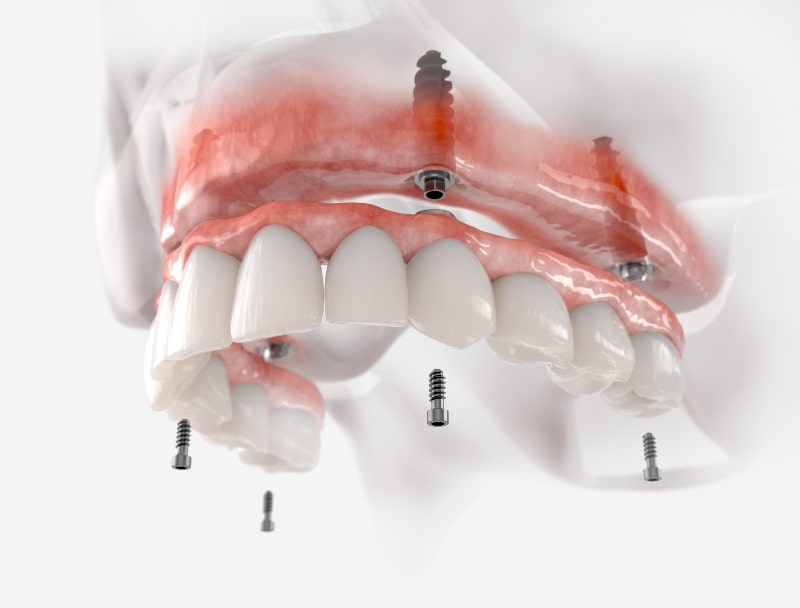

Das All-on-4®-Verfahren, entwickelt von Nobel Biocare, ist eine bahnbrechende Lösung für Patienten mit vollständigem Zahnverlust und besticht durch seine Zeit- und Kosteneffizienz. Mit nur vier (oder bei All-on-6® sechs) Implantaten pro Kiefer wird ein kompletter Zahnbogen stabil verankert. Dabei werden zwei Implantate im Frontbereich gerade eingesetzt, während die seitlichen in einem Winkel von 35 bis 45 Grad positioniert werden, um den vorhandenen Kieferknochen optimal zu nutzen. Diese clevere Technik schont empfindliche Strukturen wie Kieferhöhlen im Oberkiefer und den Nervenkanal im Unterkiefer, wodurch in den meisten Fällen kein aufwendiger Knochenaufbau nötig ist.

Festsitzende Brücke auf vier oder sechs Implantaten: Mit nur vier oder sechs strategisch platzierten Implantaten pro Kiefer wird ein gesamter Zahnbogen stabil und dauerhaft versorgt. Diese Technik nutzt das vorhandene Kieferknochenvolumen optimal und schont sensible Bereiche wie Nerven oder Kieferhöhlen, was eine sichere und effiziente Behandlung gewährleistet. Das Ergebnis ist ein natürliches, ästhetisches Lächeln, das sich wie eigene Zähne anfühlt.

Implantation (Tag 1): In nur 1–2 Stunden pro Kiefer werden Restzähne (falls nötig) entfernt, 4–6 Nobel Biocare-Implantate gesetzt und eine Abformung genommen. Danach gehen Sie für 24 Stunden nach Hause.